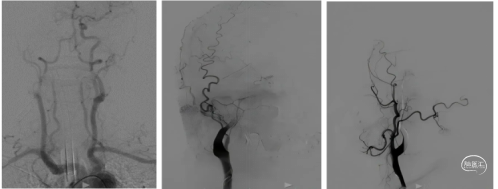

通路建立:8F短鞘,交换8F长鞘、5F多功能导管行脑血管。造影示:左侧颈总动脉闭塞,右侧颈内动脉-前交通动脉向左侧大脑中动脉部分代偿供血;左侧大脑中动脉下干闭塞。

8F长鞘引至左侧颈总动脉,088颅内血栓抽吸导管至颈总动脉-颈内动脉C4段抽吸出大量暗红色血栓。

抽吸后造影示:左侧颈总动脉复通,未见明显血栓逃逸;左侧大脑中动脉下干闭塞同术前。

微导管超选至下干近心端推注5ml替罗非班,后造影示下干部分再通,颈内动脉造影示左侧颈内动脉-大脑中动脉复通,eTICI 3级。